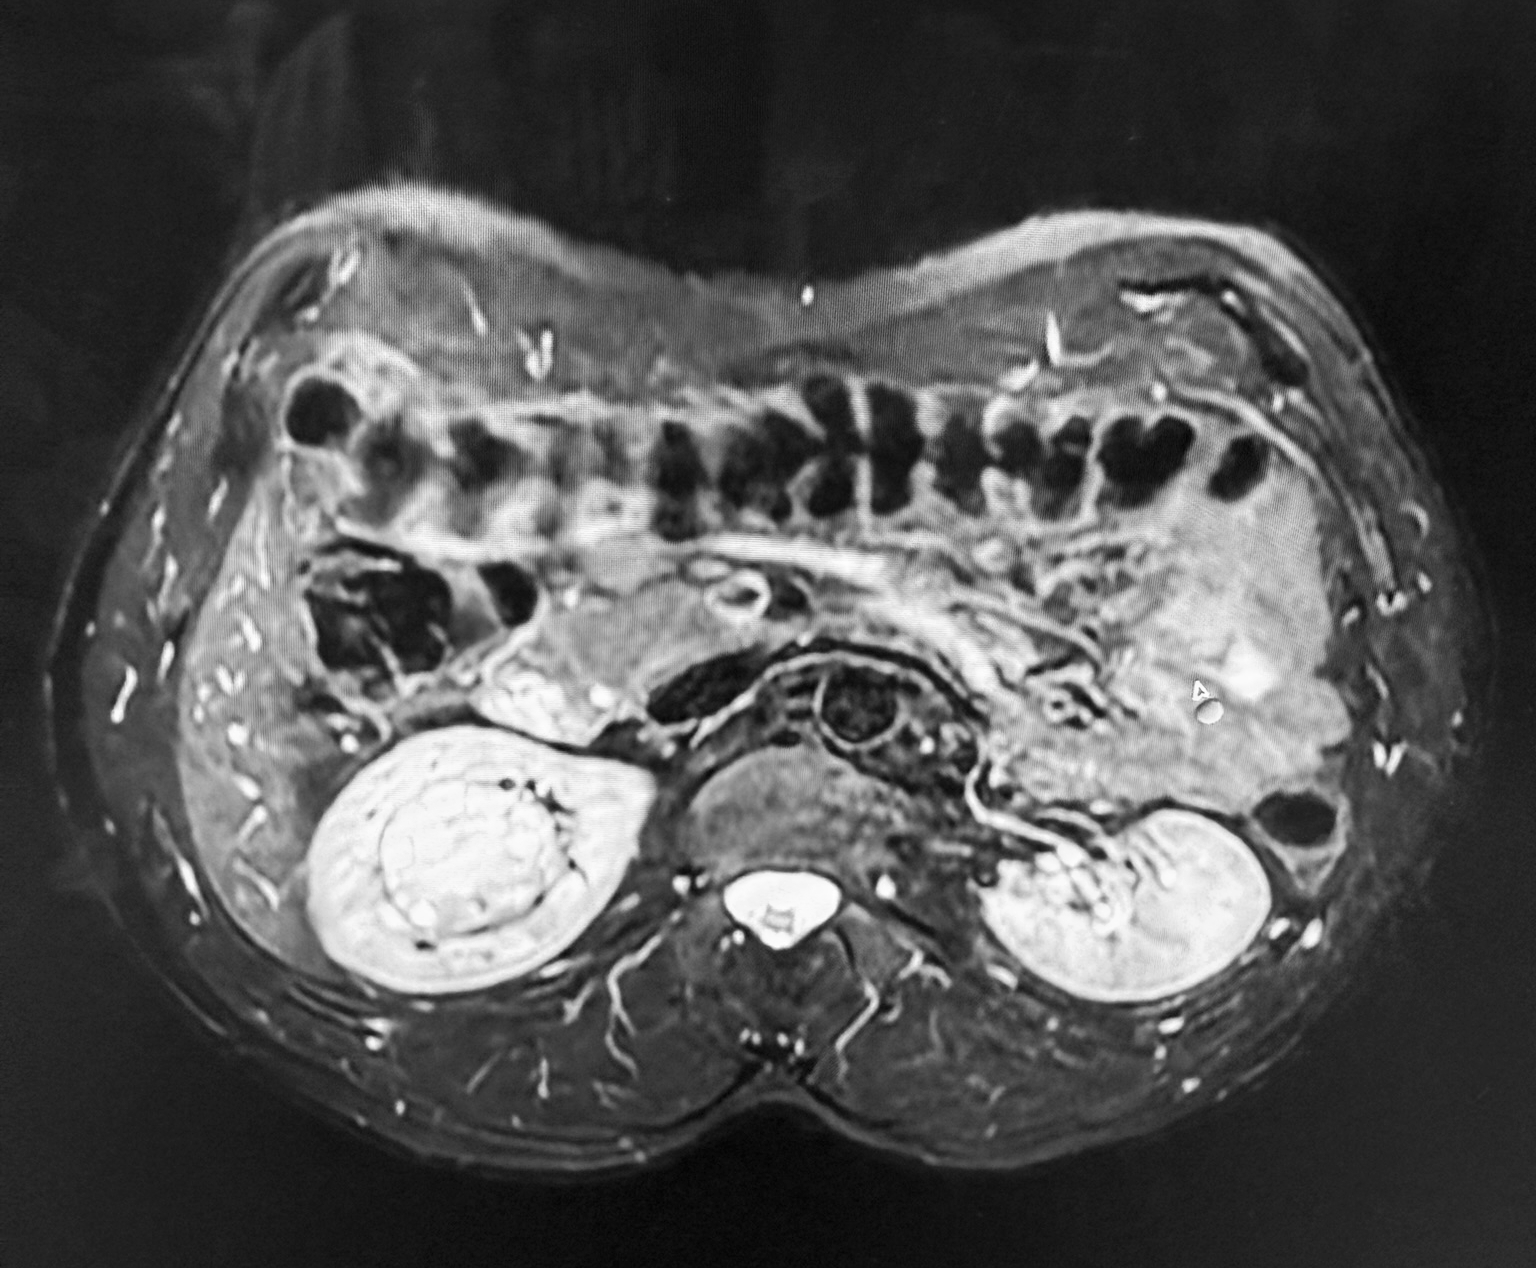

Stan przed operacją (fot. Przemysław Mitura)

Większość nowotworów nerek rośnie w sposób egzofityczny, czyli wystaje poza obrys narządu, co znacznie ułatwia ich operacyjne usunięcie. W przypadku 44-letniego pacjenta było inaczej. Lekarze zdiagnozowali u chorego guz endofityczny. Nowotwór znajdował się w samym centrum nerki.

- To była wyjątkowa operacja. Zwykle zmiany mają dwa lub trzy centymetry i są położone na brzegu nerki, dlatego ich usunięcie nie sprawia większych trudności. W przypadku 44-letniego pacjenta guz osiągnął wielkość piłki tenisowej i był ukryty w miąższu narządu. Sytuację komplikował fakt, że leżał w bezpośrednim sąsiedztwie naczyń nerkowych. Aby go usunąć, trzeba było naciąć nerkę, wypreparować zmianę i zamknąć ubytek. Była to procedura bardzo trudna technicznie i obarczone ryzykiem. Zabieg był możliwy dzięki systemowi robotycznemu da Vinci. Umożliwia on operację w powiększeniu i obrazie 3D oraz pozwala precyzyjnie zszyć głęboki ubytek po guzie. Wykonanie zabiegu bez użycia tej technologii byłoby bardzo trudne, wiązałoby się z ogromnym ryzykiem uszkodzenia naczyń i koniecznością usunięcia całej nerki — mówi dr n. med. Przemysław Mitura, pełniący obowiązki Lekarza Kierującego Klinicznym Oddziałem Urologii i Onkologii Urologicznej Uniwersyteckiego Szpitala Klinicznego Nr 4 w Lublinie.